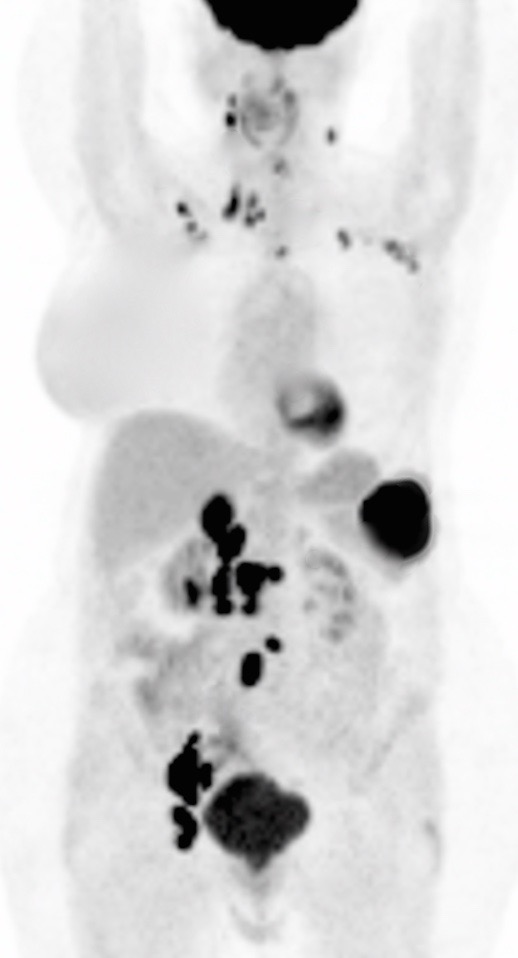

• Valuable diagnostic tool for locally advanced disease, to determine nodal status and potential distant metastatic disease (if no evidence of regional or distant disease, initial management is surgical).

The size, metabolic activity & location of the primary lesion and representative metastatic lesions are reported.

Primary Lesion:

• Nearly every cervical cancer ≥ 8.0 mm is intensely FDG avid (MRI, however, is still considered the best modality for evaluating tumor size and invasion).

Metastatic Disease:

• Direct invasion of adjacent structures.

• Lymphatic spread to pelvic and retroperitoneal lymph nodes.

• Hematogenous spread, often to lungs, liver, and bone.